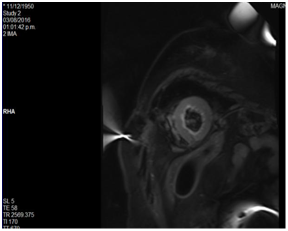

Magnetic resonance imaging

Four chamber apical cut at T2 phase where we observe an absence of a late highlight of the left ventricle (Figure 5). Short axis apical cut at black sequence phase where we observe a hyperintense highlight at the apical endocardium (Figure 6).

Figure 6